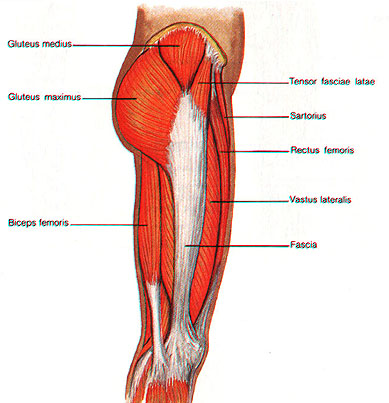

Muscle on outside of clearance thigh

Muscle on outside of clearance thigh, Anatomy Of Human Thigh Muscles Greeting Card clearance

Muscle on outside of clearance thigh

Anatomy Of Human Thigh Muscles Greeting Card

Muscles of the Human Body

Product Name: Muscle on outside of clearance thighMuscle Strains in the Thigh Florida Orthopaedic Institute clearance, Lateral leg pain more than just the IT Band Revo Physiotherapy clearance, 6 Power Packed Outer Thigh Exercises For Lower Body Strength DMoose clearance, 10 Best Thigh Exercises For Leg Day Workouts Steel Supplements clearance, Diagnosing Lateral Thigh Pain IT band syndrome Hip Bursitis and clearance, Can Rolling Your IT Band Make It Worse Functional Performance clearance, Thigh muscles side view Human anatomy Leg anatomy Human muscle clearance, Quad Muscles Function and Anatomy clearance, Rolling of the IT band anatomy of outer thigh muscles blog post clearance, Vivian Grisogono ABOUT THE FRONT THIGH MUSCLES clearance, Iliotibial band syndrome ITBS clearance, Adductor muscles of the hip Wikipedia clearance, The Secret to Resolving IT Band Syndrome using Thai Massage Thai clearance, Professor Ernest Schilders The London Hip Arthroscopy Centre clearance, Muscles of the Posterior Thigh Hamstrings Damage TeachMeAnatomy clearance, Runners Knee also known as ITB Syndrome Do You Have It and How clearance, The Physio Detective The ITB 5 things you probably haven t clearance, Diagnosing Lateral Thigh Pain IT band syndrome Hip Bursitis and clearance, Vivian Grisogono ABOUT THE FRONT THIGH MUSCLES clearance, Anatomy Of Human Thigh Muscles Greeting Card clearance, Muscles of the Human Body clearance, Understanding Iliotibial Band Syndrome Saint Luke s Health System clearance, Diagnosing Lateral Thigh Pain IT band syndrome Hip Bursitis and clearance, Meralgia paresthetica Symptoms and causes Mayo Clinic clearance, Foam rolling IT band Dos and don ts clearance, What is the Vastus Lateralis Muscle Orchard Health Clinic clearance, What is the muscle on the back of your thigh Quora clearance, IT band Friction Syndrome Ortho Rhode Island clearance, Why does the top of my left thigh ache when raising it up Quora clearance, Anatomy of Leg Muscles Plus How to Make the Most of Leg Exercises clearance, Meralgia Paresthetica Neuromuscular and Electrodiagnostic Clinic clearance, Soft Tissue Reconstruction of the Lateral Thigh and Hip SpringerLink clearance, Why Is Your Thigh In Pain 6 Common Causes Carex clearance, Anatomy of the Hamstring Upper Leg clearance, Muscle Knots in Side of Leg IT Band Tiger Tail USA clearance, Front Thigh Pain Anterior Thigh Pain Symptoms Causes Treatment clearance, Pelvic hip and thigh muscles of the right side of the body Part clearance, Outer Quad Exercises 7 Must Do Exercises Fitbod clearance, The Hip Abductor Muscles Trochanteric Bursa and Lateral Outside clearance, Muscles of the hips and thighs Human Anatomy and Physiology Lab clearance, Anatomy of the Piriformis Muscle Spine health clearance, Why Does The Outside Of My Hip Hurt What to Do About It clearance, Vastus lateralis muscle Wikipedia clearance, What is IT Band Syndrome and How Can I Fix It clearance, IONA Physiotherapy WHAT AND WHERE IS THE ILIOTIBIAL BAND ITB clearance, Groin Strain Symptoms Causes Treatment Rehabilitation Exercises clearance, Simple Ways to Stretch Your Outer Thighs 9 Steps with Pictures clearance, Meralgia Paresthetica Causes Symptoms Treatment clearance, Knee Muscles Anatomy Function Injuries Knee Pain Explained clearance, How to Cure Thigh Muscle Pain clearance.